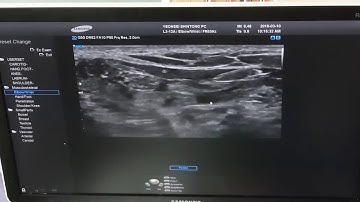

Tibial nerve hydrodissection